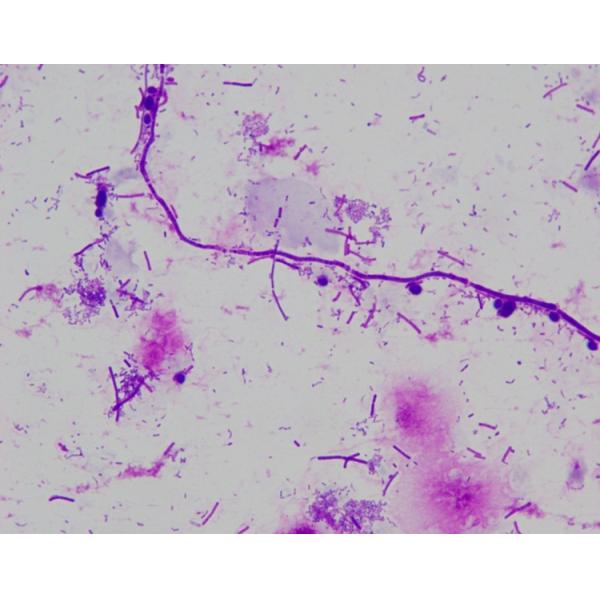

②Candida (Yeast): Stained dark blue, with visible budding spores and slender, straight pseudohyphae.

④Leptothrix: Long and thin, appearing gray-blue.

⑤Gonococci: Blue, typically kidney-shaped and often found inside or outside white blood cells and tissue cells. Note that staphylococci commonly appear in female vaginal smears, with staining results similar to gonococci, also appearing in pairs as diplococci. Therefore, interpretation of gonococci requires great caution.⑥Gardnerella: Blue, coccobacillary in shape.